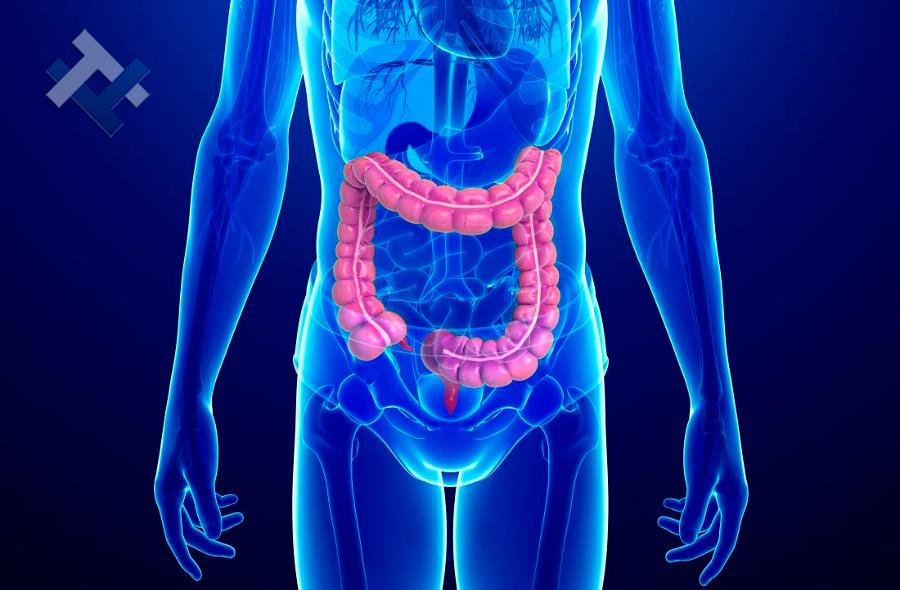

Παθήσεις Λεπτού και Παχέος Εντέρου:

- Ειλεός λεπτού εντέρου

- Εκκολπωμάτωση (Εκκολπωματίτιδα) σιγμοειδούς

- Καρκίνος παχέος εντέου

- Κολοστομίες

- Port χημειοθεραπείας

Παθήσεις Λεπτού και Παχέος Εντέρου:

- Ειλεός λεπτού εντέρου

- Εκκολπωμάτωση (Εκκολπωματίτιδα) σιγμοειδούς

- Καρκίνος παχέος εντέου

- Κολοστομίες

- Port χημειοθεραπείας

Ο Γενικός Χειρουργός Λιάγκος Γεώργιος MD PhD εκτελεί τις επεμβάσεις Λαπαροσκοπικά, Ενδοσκοπικά, Ανοιχτά Ελάχιστα Επεμβατικά και με Laser. Η θεραπεία εξατομικεύεται σε κάθε ασθενή ανάλογα με τις ανάγκες του. Αναλαμβάνει περιπτώσεις όπως κήλες και κοιλιοκήλες (αντιμετώπιση βουβωνοκήλης, αντιμετώπιση ομφαλοκήλης, θεραπεία επιγαστρικής κήλης, κήλη των αθλητών (Σύνδρομο κοιλιακών προσαγωγών), αντιμετώπιση μετεγχειρητικής κήλης, θεραπεία Μηροκήλης), πέτρες στη χοληδόχο κύστη, λαπαροσκοπική χολοκυστεκτομή, αντιμετώπιση Κύστη Κόκκυγος με λέιζερ (laser), παθήσεις πρωκτού, χειρουργική laser σύγχρονων κυκλικών ινών (αιμορροΐδες αντιμετώπιση, θεραπεία αιμορροϊδων με laser (LHP), αφαίρεση αιμορροΐδων με υπερήχους (HALL-RAR), χωρίς Χειρουργείο με ελαστικούς δακτυλίους (Τεχνική BARON-RBL), θεραπεία ραγάδας πρωκτού (Ραγάδα δακτυλίου), θεραπεία περιεδρικού συριγγίου, θεραπεία περιεδρικού αποστήματος, κονδυλώματα πρωκτού Θεραπεία, δερματικό ράκος (Skin tag) εκτομή, αντιμετώπιση Kνησμού, καρκίνος πρωκτού θεραπεία), παθήσεις Δέρματος, χειρουργική με laser CO2, αφαίρεση μορφωμάτων δέρματος - βιοψίες, αφαίρεση ελιάς (Σπίλου), σμηγματογόνος κύστης θεραπεία, αφαίρεση λιπώματος, είσφρυση όνυχος χειρουργείο, καρκίνος δέρματος θεραπεία, οξεία σκωληκοειδίτιδα, παθήσεις Λεπτού και Παχέος Εντέρου, ειλεός λεπτού εντέρου, εκκολπωμάτωση (Εκκολπωματίτιδα) σιγμοειδούς, καρκίνος παχέος εντέου, κολοστομίες, port χημειοθεραπείας κ.α.

Ο Γενικός Χειρουργός Λιάγκος Γεώργιος MD PhD εκτελεί τις επεμβάσεις Λαπαροσκοπικά, Ενδοσκοπικά, Ανοιχτά Ελάχιστα Επεμβατικά και με Laser. Η θεραπεία εξατομικεύεται σε κάθε ασθενή ανάλογα με τις ανάγκες του. Αναλαμβάνει περιπτώσεις όπως κήλες και κοιλιοκήλες (αντιμετώπιση βουβωνοκήλης, αντιμετώπιση ομφαλοκήλης, θεραπεία επιγαστρικής κήλης, κήλη των αθλητών (Σύνδρομο κοιλιακών προσαγωγών), αντιμετώπιση μετεγχειρητικής κήλης, θεραπεία Μηροκήλης), πέτρες στη χοληδόχο κύστη, λαπαροσκοπική χολοκυστεκτομή, αντιμετώπιση Κύστη Κόκκυγος με λέιζερ (laser), παθήσεις πρωκτού, χειρουργική laser σύγχρονων κυκλικών ινών (αιμορροΐδες αντιμετώπιση, θεραπεία αιμορροϊδων με laser (LHP), αφαίρεση αιμορροΐδων με υπερήχους (HALL-RAR), χωρίς Χειρουργείο με ελαστικούς δακτυλίους (Τεχνική BARON-RBL), θεραπεία ραγάδας πρωκτού (Ραγάδα δακτυλίου), θεραπεία περιεδρικού συριγγίου, θεραπεία περιεδρικού αποστήματος, κονδυλώματα πρωκτού Θεραπεία, δερματικό ράκος (Skin tag) εκτομή, αντιμετώπιση Kνησμού, καρκίνος πρωκτού θεραπεία), παθήσεις Δέρματος, χειρουργική με laser CO2, αφαίρεση μορφωμάτων δέρματος - βιοψίες, αφαίρεση ελιάς (Σπίλου), σμηγματογόνος κύστης θεραπεία, αφαίρεση λιπώματος, είσφρυση όνυχος χειρουργείο, καρκίνος δέρματος θεραπεία, οξεία σκωληκοειδίτιδα, παθήσεις Λεπτού και Παχέος Εντέρου, ειλεός λεπτού εντέρου, εκκολπωμάτωση (Εκκολπωματίτιδα) σιγμοειδούς, καρκίνος παχέος εντέου, κολοστομίες, port χημειοθεραπείας κ.α.